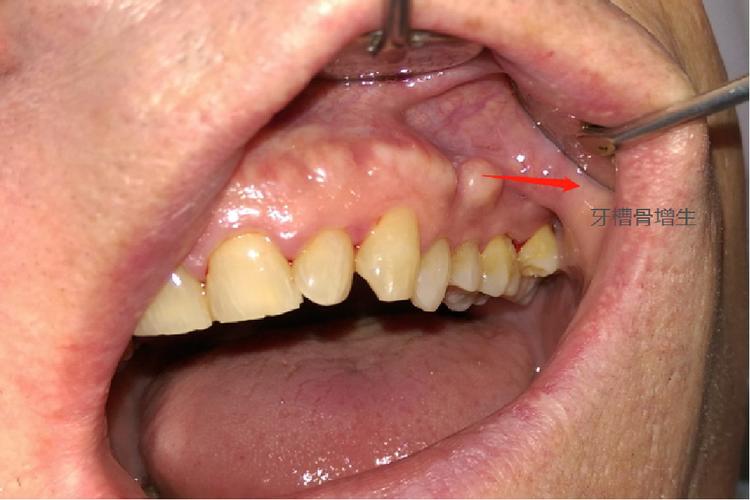

但若增生过度或发生在异常位置,则可能发展为“病理性增生”,其发生与多种因素相关:一是矫治力不当,如力量过大或持续时间过长,导致牙槽骨过度修复,形成骨赘或骨皮质增厚;二是患者个体差异,如青少年患者骨改建活跃,若矫正方案未充分考虑生长潜力,可能出现代偿性增生;三是全身性疾病影响,如甲状旁腺功能亢进、成骨不全等骨代谢异常疾病,会干扰骨吸收与重建的平衡,导致异常骨增生;四是局部因素,如牙周炎未得到控制,炎症刺激骨组织过度增生,或矫正过程中口腔卫生不佳,引发牙槽骨感染性增生。

牙周组织损伤:病理性增生常伴随牙槽骨形态异常,如骨皮质增厚、牙槽嵴顶凸起,可能压迫牙龈组织,导致牙龈退缩、牙根暴露,或形成“骨刺”刺激牙龈,引发牙龈炎、牙周袋形成,影响牙周健康。

功能与美观影响:严重的牙槽骨增生可能导致牙根吸收(因骨组织与牙根粘连)、咬合干扰,或牙龈形态异常(如牙龈增生、不对称),影响面部美观和咀嚼功能。